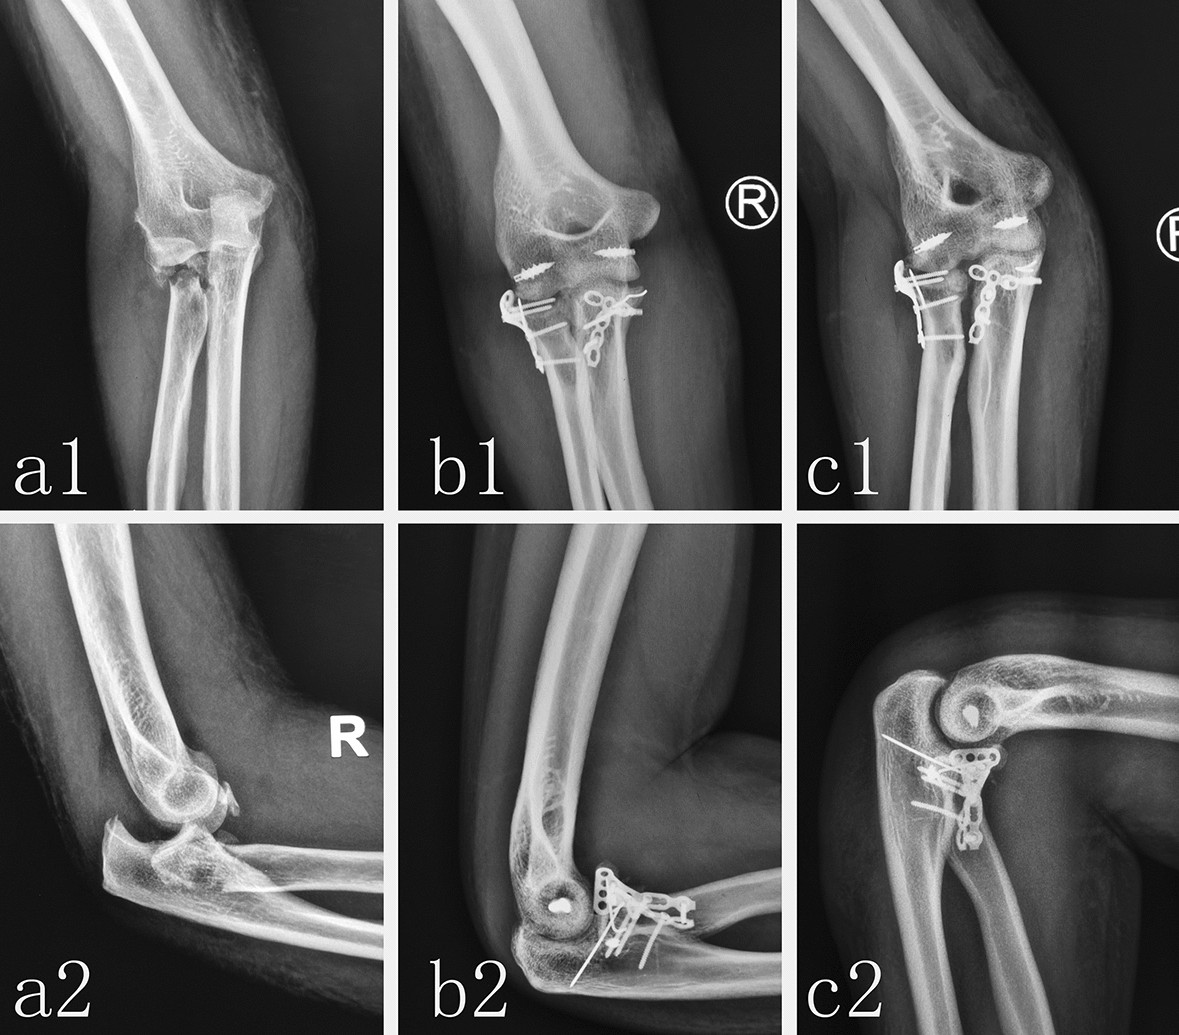

Figure 3

Radiological image of typical patient with TTE using ORIF. The preoperative anteroposterior X-ray (a1) and lateral X-ray (a2) showed the posterior dislocation of right elbow joint, the fracture of radial head and coronoid process. An anteroposterior X-ray (b1) and lateral X-ray (b2) at postoperative follow-up showed that the fracture of coronoid process and radial head were fixed by miniplate and the LCL and MCL of elbow were repaired by suture anchor. An anteroposterior X-ray (c1) and lateral X-ray (c2) at 6-months postoperative follow-up showed that fracture had healed well and the dislocation and instability of elbow were not observed.